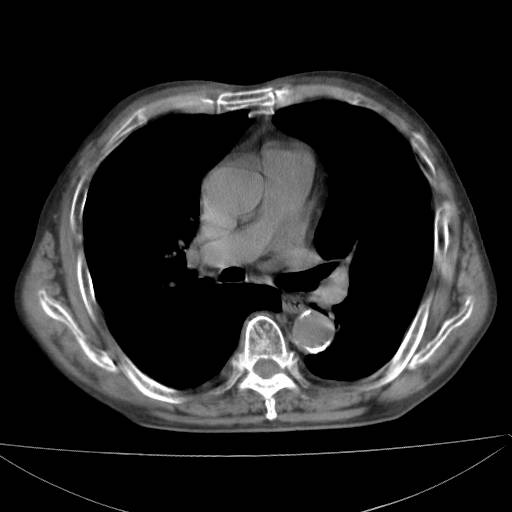

以下是引用zjzjr在2006-12-6 19:04:00的发言:[br]左肺上叶尖后段可见椭圆形高密度影,其内可见点状钙化影,周围可见卫星病灶.首先考虑结核,双侧少量胸腔积液.

以下是引用李世军在2006-12-6 19:54:00的发言:[br]左肺上叶尖后段可见椭圆形高密度影,其内可见点状钙化影,周围可见卫星病灶.首先考虑结核,双侧少量胸腔积液. [br] [br] 双肺轻度肺气肿,左肺上叶后段见多发斑片状密度增高影,周围见少许斑点状卫星病灶,双侧胸膜增厚粘连,纵隔内未见明显改变,考虑结核可能性大,请结合临床或增强扫描. [br] [br]

以下是引用13081830109在2006-12-6 19:35:00的发言:[br]左肺上叶尖后段可见椭圆形高密度影,其内可见点状钙化影,周围可见卫星病灶.首先考虑结核,双侧少量胸腔积液.

以下是引用守望可可西里在2006-12-7 0:01:00的发言:[br][quote]以下是引用zjzjr在2006-12-6 19:04:00的发言:[br]左肺上叶尖后段可见椭圆形高密度影,其内可见点状钙化影,周围可见卫星病灶.首先考虑结核,双侧少量胸腔积液.